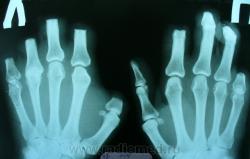

Пациент отпраздновал Рождество и прикорнул на свежем воздухе. В результате - ампутация пальцев рук и ног. Первый снимок сделан в ближайшие дни после операции. До сих пор п/опер. раны на пальцах рук не эпителизировались. Вчера проведено контрольное исследование. Ваше мнение, уважаемые коллеги, что это, недостаточный уровень ампутации? Остеомиелит? И то и другое?

А остеомиелит помоему есть.

При осмотре в ранах 3-4 пальцев правой кости и 3 и 5 п-в левой мелкие костные фрагменты.

Ваши снимки, после обработки.